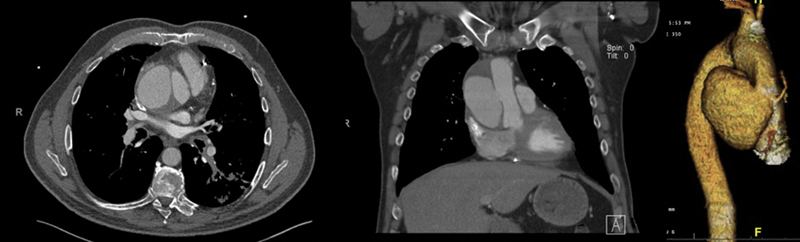

背景对于严重的左主干冠状动脉疾病患者,手术重建术后会出现许多已知的并发症。病例描述:本病例报告重点介绍了一例在冠脉搭桥术后2年出现主动脉假性动脉瘤和夹层的患者的术前检查、手术入路和术后处理。结论冠状动脉旁路移植术(CABG)后并发主动脉假性动脉瘤合并升主动脉夹层是一种罕见的并发症,在文献中几乎没有报道。

Background  There are many known complications that occur after surgical revascularization for patients with significant left main coronary artery disease. Case Description  This case report highlights the preoperative workup, surgical approach, and postoperative management of a patient who presents with an aortic pseudoaneurysm and dissection 2 years after the index CABG. Conclusion  The development of an aortic pseudoaneurysm in combination with an ascending aortic dissection after prior coronary artery bypass grafting (CABG) is a rare compilation of complications that has scarcely been reported in the literature.